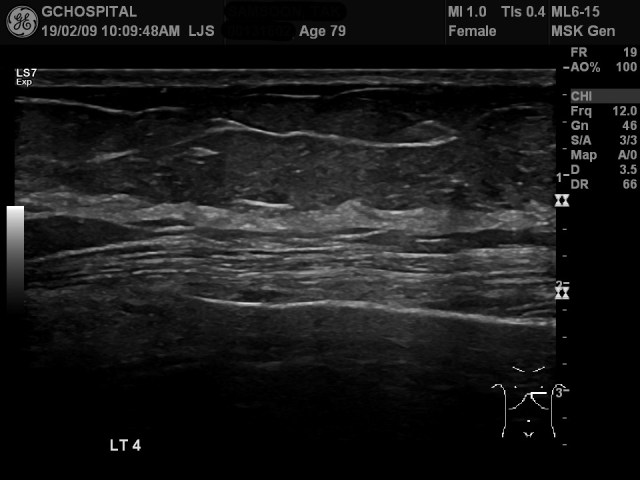

왼쪽 5번째 늑골에서는 더 뚜렷하게 bone cortex가 끊어져 있으며, subperiosteal hemorrhage의 양도 네번째 늑골보다 더 많습니다. scaleneus anterior muscle이 출혈에 의해 벌어져서 위로 밀려나있는 양상도 더 뚜렷하게 보입니다.